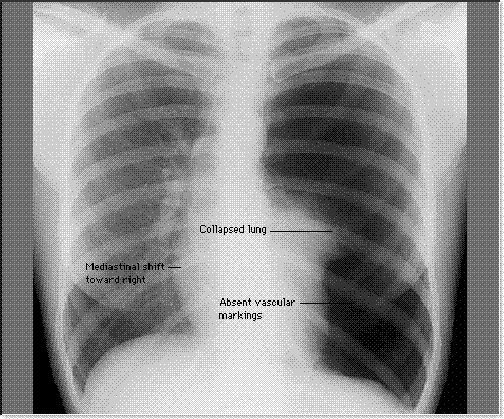

Bayangan udara dalam rongga pleura memberikan bayangan radiolusen yang tanpa struktur jaringan paru (avascular pattern) dengan batas paru berupa garis radioopak tipis yang berasal dari pleura visceral (gambar 1 dan 2)(2).

Pada foto terlihat bayangan udara dari pneumotoraks yang berbentuk cembung, yang memisahkan pleura parietalis dengan pleura viseralis. Bila pneumotoraksnya tidak begitu besar, foto dengan pernafasan dalam (inspirasi penuh) pun tidak akan menunjukkan kelainan yang jelas. Dalam hal ini dianjurkan membuat foto dada dengan inspirasi dan ekspirasi penuh. Selama ekspirasi maksimal udara dalam rongga pleura lebih didorong ke apeks, sehingga rongga intrapleura di apeks jadi lebih besar. Selain itu terdapat perbedaan densitas antara jaringan paru dan udara intrapleura sehingga memudahkan dalam melihat pneumotoraks, yakni kenaikan densitas jaringan paru selama ekspirasi tapi tidak menaikkan densitas pneumotoraks(1).

Jika pneumotoraks luas, akan menekan jaringan paru ke arah hilus atau paru menjadi kuncup/kolaps di daerah hilus dan mendorong mediastinum ke arah kontralateral. Selain itu sela iga menjadi lebih lebar(2). Udara dalam ruang pleura jadi lebih radiolusen dibandingkan paru-paru yang bersebelahan dengan pneumotoraks tersebut, terutama sekali jika paru-paru berkurang volumenya, dimampatkan atau terkena penyakit yang meningkatkan kepadatan paru-paru(3).

Bayangan udara dalam rongga pleura memberikan bayangan radiolusen yang tanpa struktur jaringan paru dengan batas paru berupa garis radioopak tipis berasal dari pleura viresal.

Jika pneumothoraks luas, akan menekan jaringan paru ke arah hilus atau paru menjadi kuncup/kolaps di daerah hilus mendorong mediastinum ke arah kontralateral. Selain itu juga iga lebih lebar.